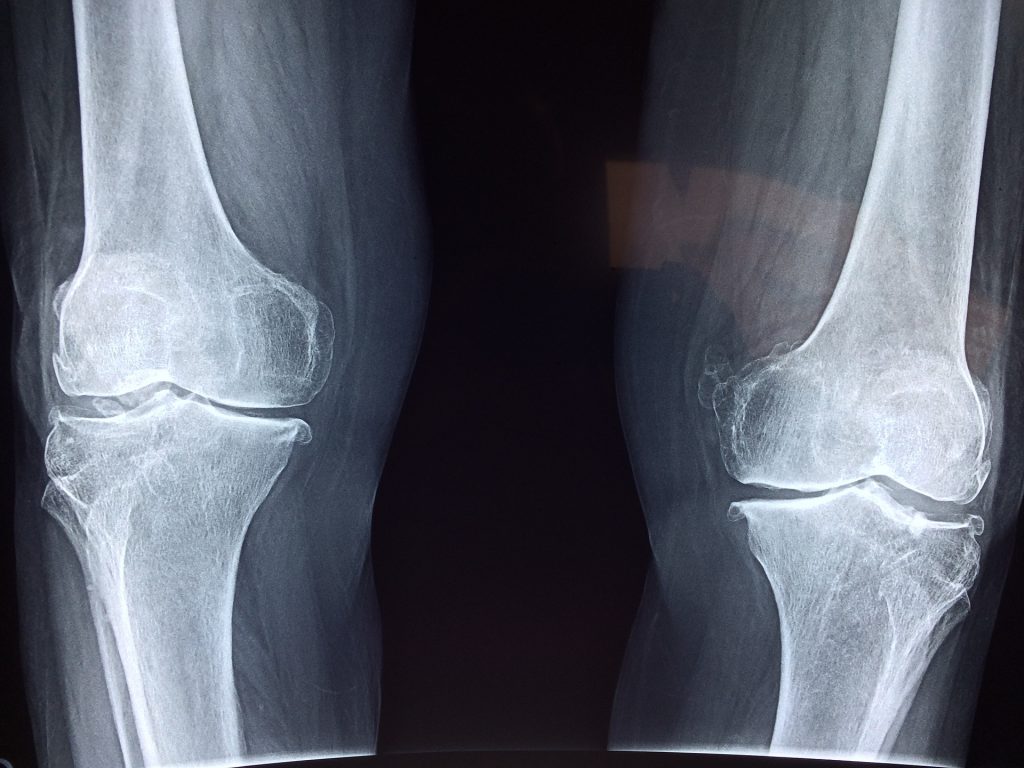

Knee Injury Compensation for Injured WorkersWalker Law Group has over two decades of experience in assisting workers injured in the workplace to achieve the best possible compensation. Walker Law Group are approved by the WorkCover Independent Review Office which has established the Independent Legal Assistance and Review Service. Under this service free access is provided to independent legal advice for injured workers through a financial grant where there is disagreement with an injured worker's insurance company concerning entitlements.Walker Law Group works with WIRO to assist with grants of legal service or to resolve disputes that cannot be progressed. Where there is an arguable chance of success, a grant will be provided which allows Walker Law Group to assist with the particular matter.Injuries that occur in the work place are common. In particular, knee injuries frequently occur due to the fact it is a part of the body that is easily injured in a fall, collision or when turned in a direction not compatible with the knee joint.If you are an employee or sub-contractor who has experienced an injury whilst at work, for example an injury to your knee by way of a fall, collision or stress over time, you may be entitled to a considerable amount of compensation which reflects as best as possible the extent of the injury and assists with any needs which arise as a result of the injury.There are a number of aspects which require consideration before it is possible for a person to claim compensation or bring legal action for the purpose of compensating them for a work place injury.Firstly, you must be either an employee or sub-contractor who receives a wage or commission. If you are an independent contractor, you usually won't be able to make a claim against the organisation which has contracted with you.Secondly, the injury must be work related. This means the injury must have either occurred at the place at which you work, or the work for which you are paid aggravated a pre-existing injury. This includes not only physical but also psychological injuries. Further, if you are caused to suffer a disease the main cause of which is your work or it aggravated an underlying disease, you may be able to bring a claim for compensation. For example, if you work in an area which is loud and this causes damage to your hearing or deafness, or if you work in an area with chemicals which cause damage to your respiratory system including asthma, you may be entitled to compensation.If you are injured travelling to or from work, a claim for worker’s compensation will not normally be successful. If your injury involves a motor vehicle accident when travelling to or from work, it may be covered by the compulsory third party insurance scheme. If there is a 'real and substantial' connection to the injury and your employment however, a claim for compensation may be successful.Where an employee or sub-contractor is injured at work and the employer or organisation contracted with notifies their insurer of the injury, the injured party will normally receive provisional payments. Provisional payments should start within 7 days of the injury and are intended to reduce the immediate impact of an injury. It is not necessary for an insurer to accept the claim for an injured worker to start receiving provisional payments.Where an employer or contracted organisation's insurer accepts a claim for a work place injury, the injured worker may be entitled to payments on a weekly basis which are calculated as a percentage of the worker's current wage.